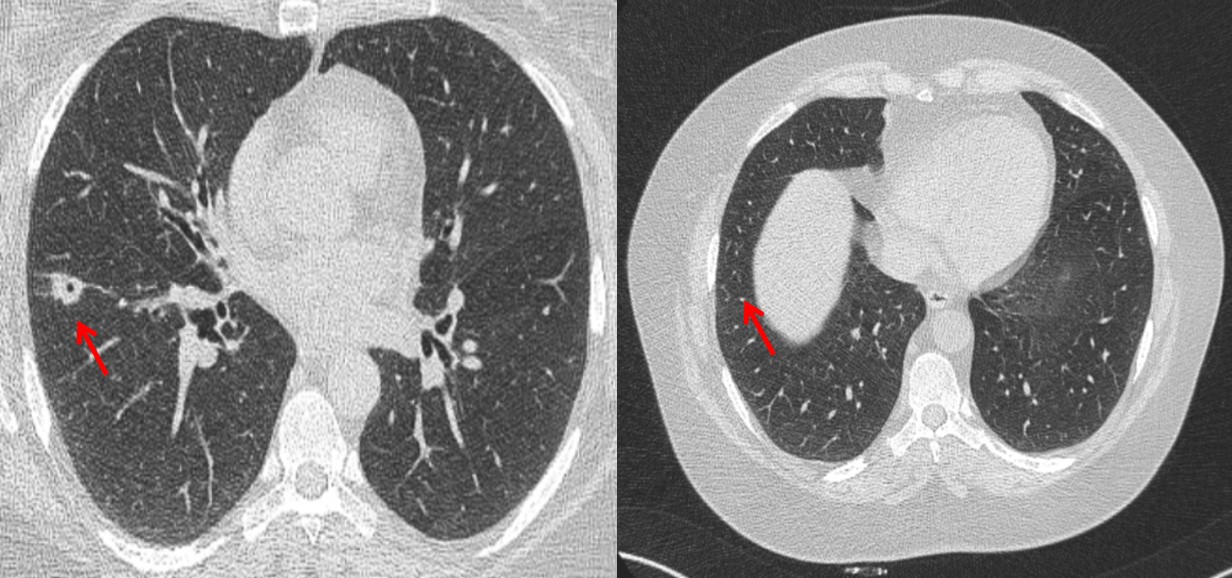

Ревматоидный артрит (РА) – это заболевание, которое, помимо поражения суставов, характеризуется системным поражением различных локализаций, в т. ч. легких. Поражение дыхательной системы встречается примерно в 30–40 % случаев и может иметь различные проявления, требующие проведения дифференциальной диагностики. Одним из проявлений являются ревматоидные узелки, которые могут приводить к образованию полостей в легких, кровохарканью и пневмотораксу.

Заключение. Представлено клиническое наблюдение за пациенткой с серопозитивным РА, у которой на фоне длительного течения заболевания появились полостные образования в легких, сопровождающиеся кровохарканьем. Были исключены другие причины, такие как тромбоэмболия легочной артерии, злокачественные новообразования, специфическая инфекция, другие системные заболевания. Также рассматривалось поражение легких вследствие приема препарата из группы ингибиторов фактора некроза опухоли-альфа (этанерцепт), однако в связи с появлением новых очагов на фоне отмены препарата данный вариант представлялся маловероятным. Важным этапом установления диагноза в данном случае явилось гистологическое исследование. В исследуемом материале – признаки легочного васкулита и ревматоидных узелков. Таким образом, было верифицировано висцеральное поражение легких при РА. На примере данного клинического наблюдения продемонстрирована необходимость проведения дифференциальной диагностики полостных образований легких при РА с инфекционными, онкологическими и другими системными заболеваниями, а также с лекарственным поражением.